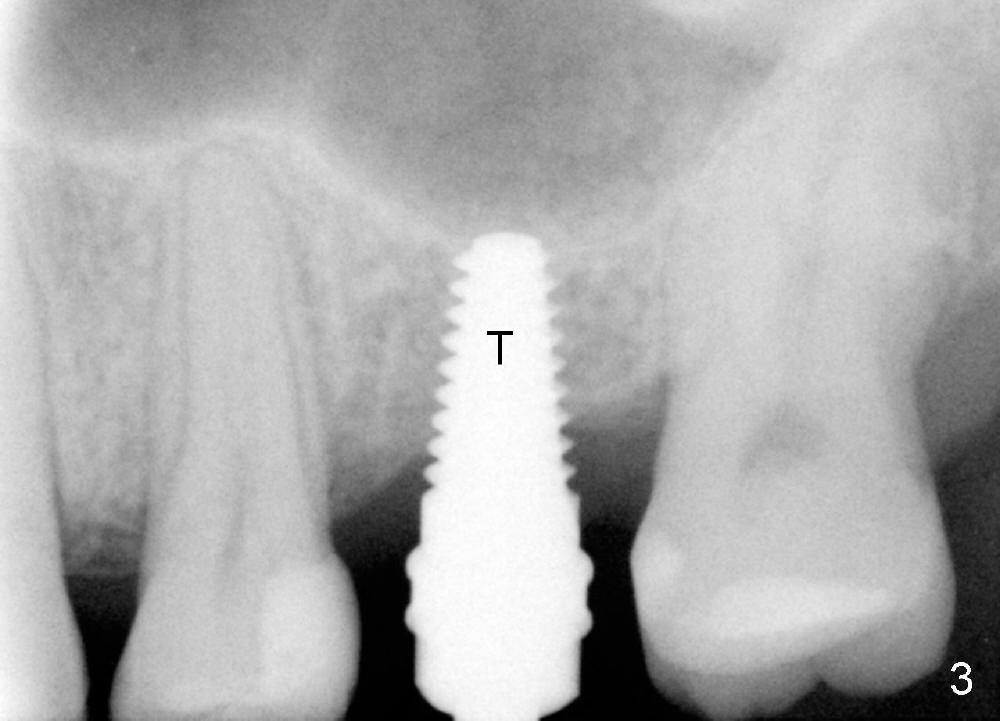

A 48-year-old lady has lost #14 for a while (Fig.1). It looks that bone density at the site of #14 is lower than that mesial to the 2nd premolar. The buccolingual width is wide clinically, although the mesiodistal distance is short (8 mm, Fig.2). A 4-mm tissue punch is used for access. When 1.5 mm pilot drill is used to start osteotomy, it feels that bone density is not low. The first bone expander (2.6 mm) cannot penetrate the bone. Therefore reamers 2.5-3.5 mm are used to increase osteotomy at the depth of 6 mm from the gingival margin. A 4.5x11 mm tap drill is inserted ~ 7 mm with resistance (Fig.3). After 5x11 mm tap, autogenous bone mixed with Osteogen is pushed into the osteotomy and upward. A 5x11 mm implant is placed with > 60 Ncm (Fig.4). After the last X-ray, the implant is torqued 5 more times so that the distal last thread may be able to be fully engaged to the bone. Fig.5 is CT coronal section at the site of #14 5 days postop (B: buccal; L: lingual). Fig.6 is taken 5 months postop with maintenance of sinus lift (*). The crown dislodges 16 months post cementation. In fact the abutment is also loose. The latter is resin bonded, followed by crown cementation (Fig.7). It appears that when the implant is 5 mm or less, the unipost should be permanently cemented in order to prevent crown displacement, particularly for a patient with bruxism and partial edentulism.